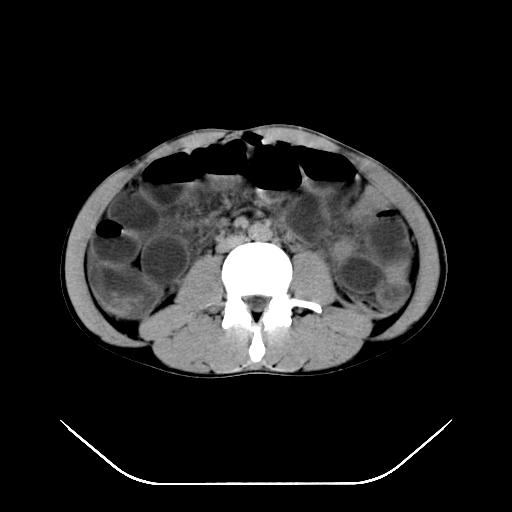

反射性肠郁张是指许多原因造成肠道吸收气体和液 功能障碍,也可造成分泌功能与动力的障碍,以致肠道内有过量的气体和液体潴积,有时只有过量的气体潴积。肠道较舒张,但不扩大,或有部分肠道轻度的扩大,这种情况叫做反射性肠郁张 ,这个病人的肠管扩张太明显了。

提示有肠梗阻的可能性?

我不同意守望可西里老师所说的有输尿管的血液凝积一说,首先从这个图像来看输尿管的走行太偏外了,输尿管是肾盂向下延续的部分,开始在腰大肌的外缘,逐渐向内偏移,接近或越过腰椎横突的外端。而守望可可西里老师所指的这段图像位置太靠外了,且总是伴行在一段肠管的前缘。第二,如果有血液的凝积,可造成肾盂肾盏的扩张积水,而这个病人的肾盂肾盏的形态一直很好。

综上所述,考虑1:左肾挫伤并包膜下血肿2:少量腹腔积液3:肠梗阻的可能

第二次ct检查后:临床医生腹水穿刺后考虑肠系膜动脉破裂,后实行剖腹探查:于空肠距离十二指肠90cm处发现肠管破裂,破裂口较小;修补后关腹。